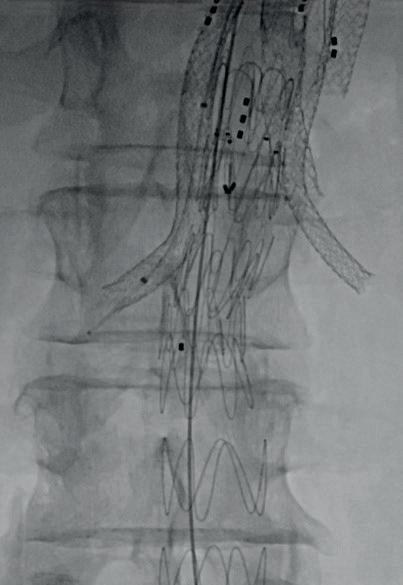

Recently conducted first-in-human procedures with a longer length of Bentley’s BeGraft Plus mark the latest in a series of moves from the company towards providing a dedicated bridging stent portfolio for fenestrated and branched endovascular aneurysm repair (FEVAR and BEVAR).

ERIC VERHOEVEN (PARACELSUS MEDICAL University and General Hospital, Nuremberg, Germany), who conducted the procedures, speaks to Vascular News to share his expert insights on the topic. He comments on the development of Bentley’s complex aortic offering from general to dedicated solutions that are “easier to use” for aortic specialists and “more effective” for patients.

The evolution of complex aortic care

Setting the scene, Verhoeven highlights the long and winding evolution of complex aortic intervention towards fenestrated and branched repair. Over the past 25 years, he says, a multitude of new stent designs and concepts have emerged with varying levels of success. Part of the challenge has been meeting the different requirements for bridging stents in both FEVAR and BEVAR, Verhoeven notes, stressing the importance of having dedicated products—rather than adapted ones—for different anatomies and clinical scenarios.

therefore requires different tools.

A need for dedicated stents

Verhoeven cites Bentley as the first company to understand the clinical need for dedicated bridging stents in FEVAR and BEVAR. He notes that, to date, the company has achieved on-label indications for the BeGraft and BeFlared in FEVAR and the BeGraft Plus in BEVAR, with the BeFlared emerging as the first dedicated stent for FEVAR and the longer BeGraft Plus, a dedicated stent in BEVAR.

Eric Verhoeven

While fenestrations are used mainly in complex abdominal aneurysms, Verhoeven elaborates, branches are adopted predominantly for thoracoabdominal aneurysms. “It’s therefore very important to understand that we need different stents,” he says.

In FEVAR, for example, Verhoeven notes that a balloon-expandable stent graft is needed due to its ability to flare and adapt to the fenestration, as well as its association with precise deployment. With BEVAR, on the other hand, both self- and balloonexpandable stents have the potential to be suitable options, with the choice depending on several factors. It is important with BEVAR to select a stent that “adapts to the situation”, Verhoeven says, noting how this can differ greatly from case to case. “Sometimes you need flexibility at different levels, sometimes you need radial force or kink resistance,” he continues, stating that the “ballgame in branched EVAR is more complex than the one in fenestrated EVAR” and

Verhoeven highlights in particular the success of the BeFlared in having achieved—in his opinion—the “ultimate goal” of a dedicated stent for fenestrations. He lists certain advantages of the BeGraft in fenestrations, including its availability in a wide range of diameters and lengths, its 6Fr compatibility, and its visibility due to a cobalt chromium stent design. On the BeFlared as a dedicated product in fenestrations, he underscores the benefits of a shorter procedure time (several minutes per target vessel), shorter fluoroscopy time (roughly one minute per

We will certainly, as users, benefit from these dedicated stents.”

target vessel), and—most importantly—easier precise positioning and the avoidance of “costly” mistakes.1

In branches, however, Verhoeven believes there is “potential for development” to find the “ideal” dedicated stent. “Will we ever have the ideal stent?” he queries, citing the need for case-dependent features as grounds for caution in seeking the perfect device.

Verhoeven’s caution rests on there being “really two or three stent designs that can be used [for BEVAR] in the correct anatomy”. By way of example, he explains: “If you work in a very narrow aorta, but there is still enough room for the branch, then you

want a bridging stent graft with the highest radial force; if you have a lot of room, that radial force is less important, but maybe kink resistance is more important and maybe flexibility at the distal landing zone to avoid kinking in the target vessel is important. “In branches, the requirements for the bridging stent are far more dependent on the anatomy. This complexity will make it difficult to build a stent that answers all requirements for all anatomies.”

Despite his reservations about the concept of an “ideal” bridging stent for BEVAR, Verhoeven expresses his confidence in the BeGraft Plus for use in this anatomy. “I think the BeGraft Plus was a very smart move,” he says.

In particular, Verhoeven points out the concurrent high radial force and kink resistance of the device, making it well suited to a broad range of BEVAR cases. “It may not fulfil all of my desires,” he comments, “but it has a very strong case to be used in branches.”

The BeGraft Plus is now on label for BEVAR, with Verhoeven having conducted the first-inhuman cases using the novel additional (longer) stent lengths of 77/78mm on 3 and 4 December at his centre in Nuremberg. Verhoeven reports that the device “worked very well” in the two cases. “We were certainly happy to have the longer BeGraft Plus, especially in emergency or off-the-shelf procedures to bridge long distances with its minimal foreshortening,” he comments.